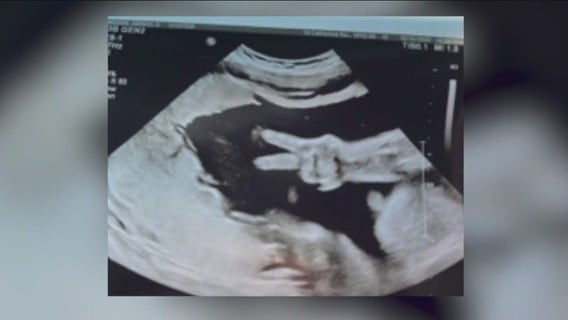

Hammond couple's baby gives 'peace sign' during ultrasound

Everyone is going ‘gaga’ over this ultrasound picture taken in northwest Indiana!